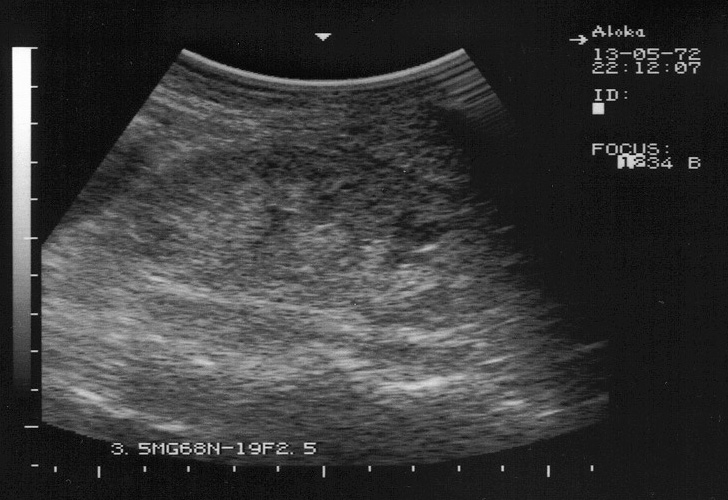

Амилоидоз почек. Renal amyloidosis

Диагноз доказан морфологически.

amyloid1.jpg